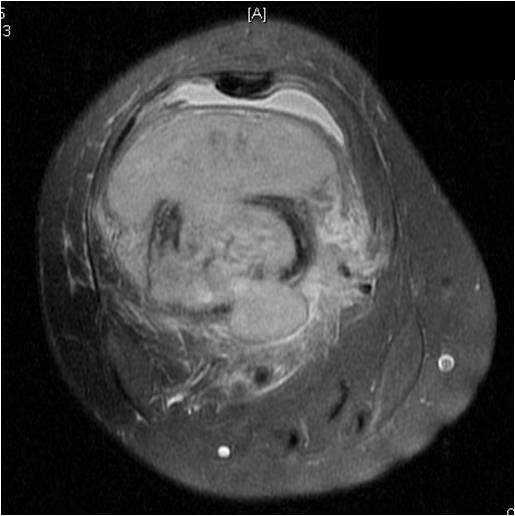

On radiographs, most MFHs of Bone are located in the metaphysis and present as purely osteolytic permeative lesions without a periosteal reaction and without mineralization (Fig. 1 &2). On MR images, MFH of Bone has ill-defined margins usually with cortical destruction of bone and extension into the soft tissues. It is usually hypo- or isointense to muscle on T1-weighted images (Fig. 3) and heterogeneous high intensity on T2-weighted images (Fig. 4-6).

Fig. 4-6: MRI Axial (Fig. 4) and (Fig. 5) T2 –weighted fat-suppressed images show a heterogeneous lesion in the distal femur. Axial T2- weighted fat suppress image (Fig. 6) demonstrates a heterogeneous lesion with hyperintense areas admixed with hypointense signal areas concordant with hemorrhage and necrosis. High grade sarcomas are commonly associated with hemorrhage and necrosis.